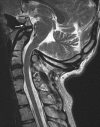

Background: The embryology of the bony craniovertebral junction (CVJ) is reviewed with the purpose of explaining the genesis and unusual configurations of the numerous congenital malformations in this region. Functionally, the bony CVJ can be divided into a central pillar consisting of the basiocciput and dental pivot and a two-tiered ring revolving round the central pivot, comprising the foramen magnum rim and occipital condyles above and the atlantal ring below. Embryologically, the central pillar and the surrounding rings descend from different primordia, and accordingly, developmental anomalies at the CVJ can also be segregated into those affecting the central pillar and those affecting the surrounding rings, respectively.

Discussion: A logical classification of this seemingly unwieldy group of malformations is thus possible based on their ontogenetic lineage, morbid anatomy, and clinical relevance. Representative examples of the main constituents of this classification scheme are given, and their surgical treatments are selectively discussed.